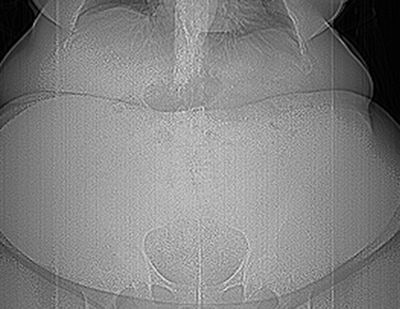

Though CT aperture diameters may be accurate in the horizontal plane, they do not account for the table thickness entering the gantry bore. The vertical diameter is actually 20 cm less than the published diameters, limiting its use in morbidly obese patients. All images courtesy of Dr. Rajeev Suri, an associate professor of vascular and interventional radiology at the University of Texas Health Science Center in San Antonio, U.S.In an e-poster presented at ESGAR 2013, Dr. Rajeev Suri, an associate professor of vascular and interventional radiology at the University of Texas Health Science Center in San Antonio, U.S., elaborated on the logistical difficulties posed by the growing obesity epidemic. These include the weight limits and aperture diameters of imaging equipment, scheduling and transport issues, working out how well the patient will fit in the imaging equipment, and modification of equipment settings to optimize image quality for the obese patient.

Digital radiograph of a 635-lb patient after a motor vehicle accident. To image this patient with CT, knowing the weight limits of the available CT scanner is critical -- most CT scanners have a weight limit of 450 lbs to 500 lbs. CT scanners available with higher weight limits include: Toshiba Medical Systems (660 lb, Aquilon One); Philips Healthcare (650 lb: Brilliance Big Bore); GE Healthcare (650 lb: Lightspeed Xtra), and Siemens Healthcare (660 lb: Somatom Definition)."Current imaging technology is limited in providing the desired quality of imaging in obese patients," he wrote. "Radiologists and technologists need to be aware of the limitations of imaging equipment and the equipment adjustments that can be made to improve image quality in obese patients. Best technique depends MORE on weight limit and aperture sizes THAN the appropriateness of the exam. Consider portable radiography or sonography equipment for patients who cannot be transported."